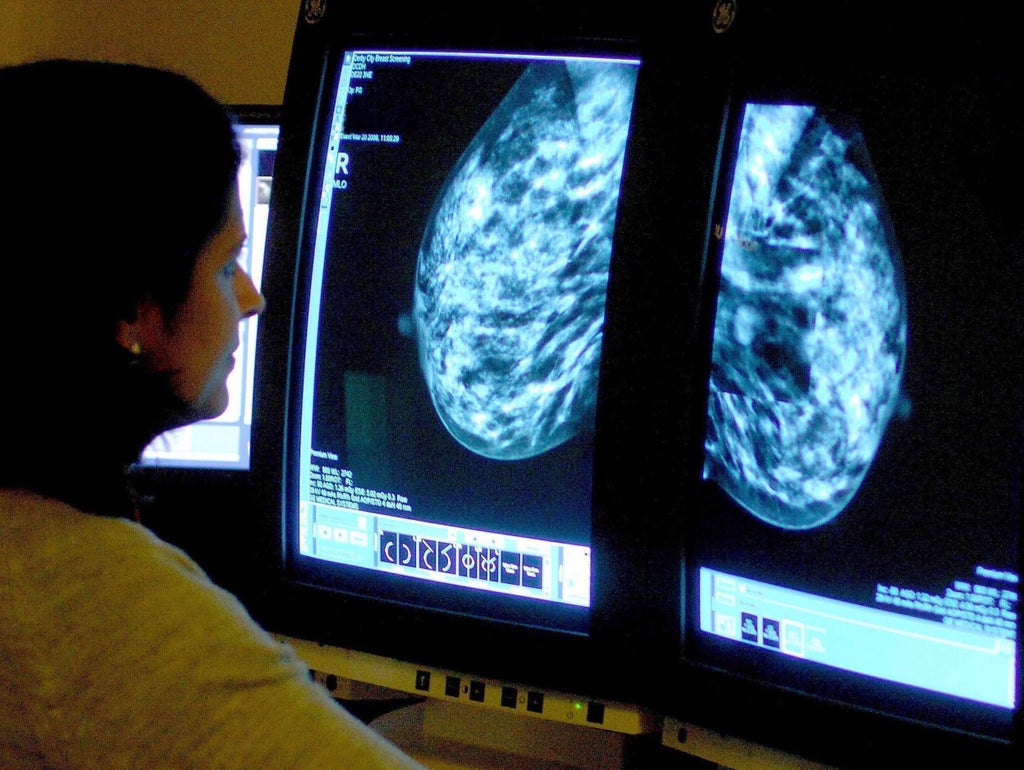

The pandemic massively disrupted breast cancer services after the NHS breast screening programme was effectively paused for several months. Routine invitations for breast screening only resumed after the first wave of the pandemic and many of these missing cases are likely to be cancers that were not picked up in screening.

Professor Charles Swanton, Cancer Research UK’s chief clinician, said: “Considering the huge disruption to cancer services, sadly, these figures are not surprising. And we’re seeing the impact of effectively pausing breast screening which detects almost a third of breast cancer cases.